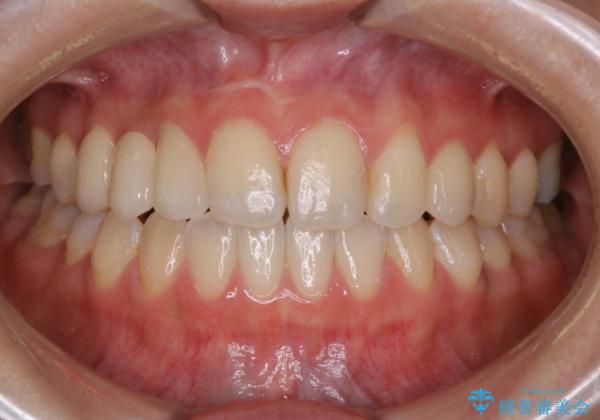

歯科技工士さんの熟練した技術により、周囲の歯としっかりなじむ天然歯のような被せ物をお作りすることが出来ました。

矯正治療と補綴治療をうまく組み合わせることで、美しい口元に仕上げることが出来ました。矯正治療、補綴治療をまとめて行える総合歯科治療を体現した治療といえます。